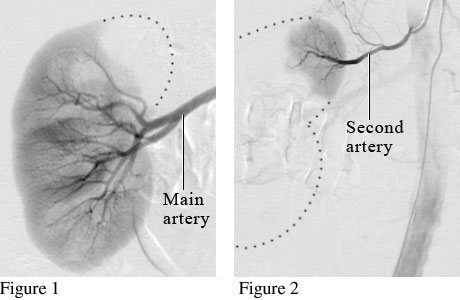

Angiogram of a Normal Kidney